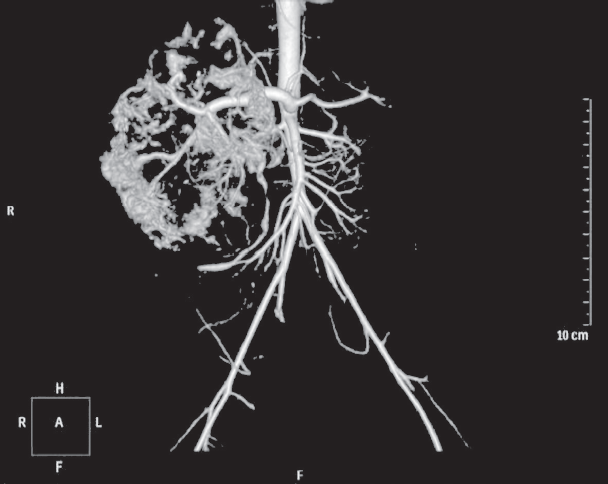

Гемангиомы — наиболее часто встречающиеся доброкачественные сосудистые образования печени детского возраста, которые могут приобретать как злокачественное течение, так и спонтанно регрессировать. На первом году жизни их распространенность составляет 10–12 %. Среди недоношенных детей распространенность гемангиом коррелирует со степенью недоношенности. Гемангиомы небольших размеров, как правило, не требуют специфического лечения и протекают бессимптомно. Образования крупных размеров могут вызывать жизнеугрожающие состояния: тяжелую тромбоцитопению с коагулопатией (синдром Казабаха – Меррита), анемию, кровоизлияние в опухоль, спонтанные и травматические разрывы опухоли, сердечную недостаточность, связанную с внутриопухолевым шунтированием кровотока, синдром абдоминальной компрессии, тяжелый гипотиреоз. Диагноз устанавливается на основании совокупности данных медицинской визуализации, лабораторной диагностики и клинической картины. В данном обзоре представлены ключевые моменты общей классификации, наиболее характерные диагностические признаки, а также базовые алгоритмы лечения гемангиом печени у новорожденных и детей первого года жизни. Также описаны 2 клинических случая новорожденных с гигантскими гемангиомами печени, которые обследовались и получали лечение в отделении патологии новорожденных и детей грудного возраста Перинатального центра Санкт-Петербургского государственного педиатрического медицинского университета с описанием особенностей течения каждого из них.